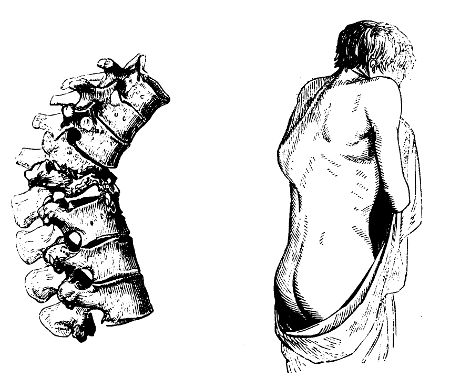

| Fractures of theSpinal Column | 560 |